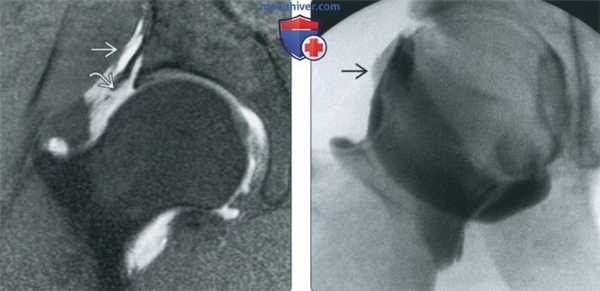

(Слева) МР-артрография в режиме Т1ВИ FS, коронарный срез: визуализируется неоднородное скопление контрастного препарата, распространяющееся через разорванную подвздошно-бедренную связку за пределы суставной капсулы.

(Справа) Артрография, передне-задняя проекция: определяется небольшой затек контрастного препарата через подвздошно-бедренную связку, обусловленный тем, что после артроскопической операции дефект суставной капсулы не был закрыт. Пациент ощущал нестабильность сустава.